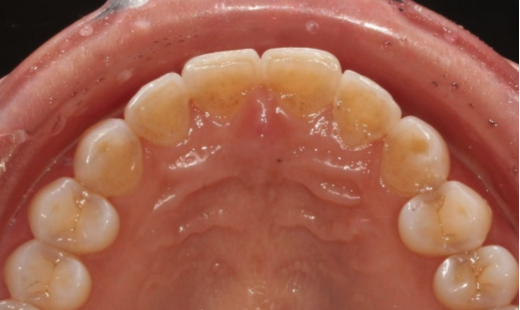

The two front teeth are protruding forward from the dental arch.

It is possible by reducing the thickness of the two protruding central incisors by shaving them down, or by making the adjacent lateral incisors relatively thicker.

Still, to proceed in the healthiest way for laminate veneers in the 50s, we performed partial orthodontic treatment on only the six front teeth, moved the two protruding central incisors back into their proper position, and then did the no-prep laminate veneers.

That way, protrusion can be prevented and there is no need to shave the teeth.

This is the condition immediately after removal of the orthodontic appliance following 4 months of partial front-tooth orthodontic treatment.

The two protruding front teeth have also been moved back into place.